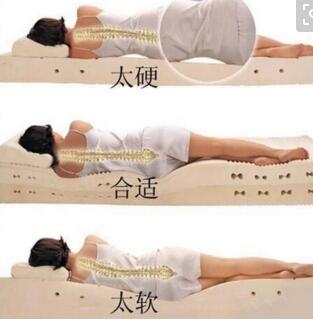

为减少颈椎的前弯,强直患者要低枕睡硬板床

无论是什么疾病大家都应该做好它的保健,及时防治疾病的复发,强 ...